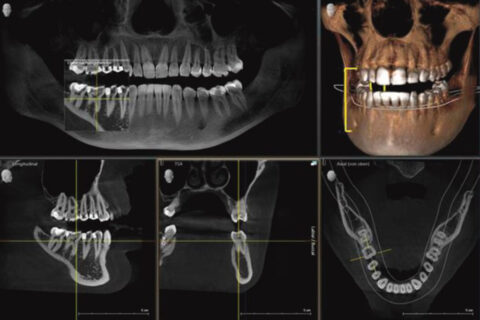

Neben der Kompetenz und Professionalität des Praxisteams ermöglichen der Einsatz moderner Technologien und die neueste technische Ausstattung zahnmedizinische Behandlungen auf höchstem Niveau.